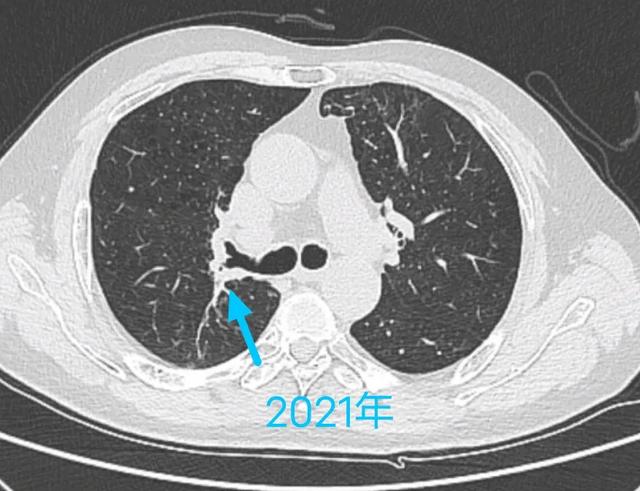

癌症从一开始就已经决定一个人的命运,治和不治都一样,是真的吗?插图3

就像这位病人是小细胞肺癌,因为发展快、转移早,查出来时就无法手术。

但他通过放化疗为主的综合治疗,目前已经带瘤生存三年半。

癌症从一开始就已经决定一个人的命运,治和不治都一样,是真的吗?插图4

这是一位中央型肺鳞癌患者,是一个老烟民,肿瘤侵犯主支气管根部,手术获益机会渺茫,选择放疗为主的综合治疗。

癌症从一开始就已经决定一个人的命运,治和不治都一样,是真的吗?插图5

这是去年年底做的复查,肿瘤萎缩残留放疗后改变,目前几乎无症状。